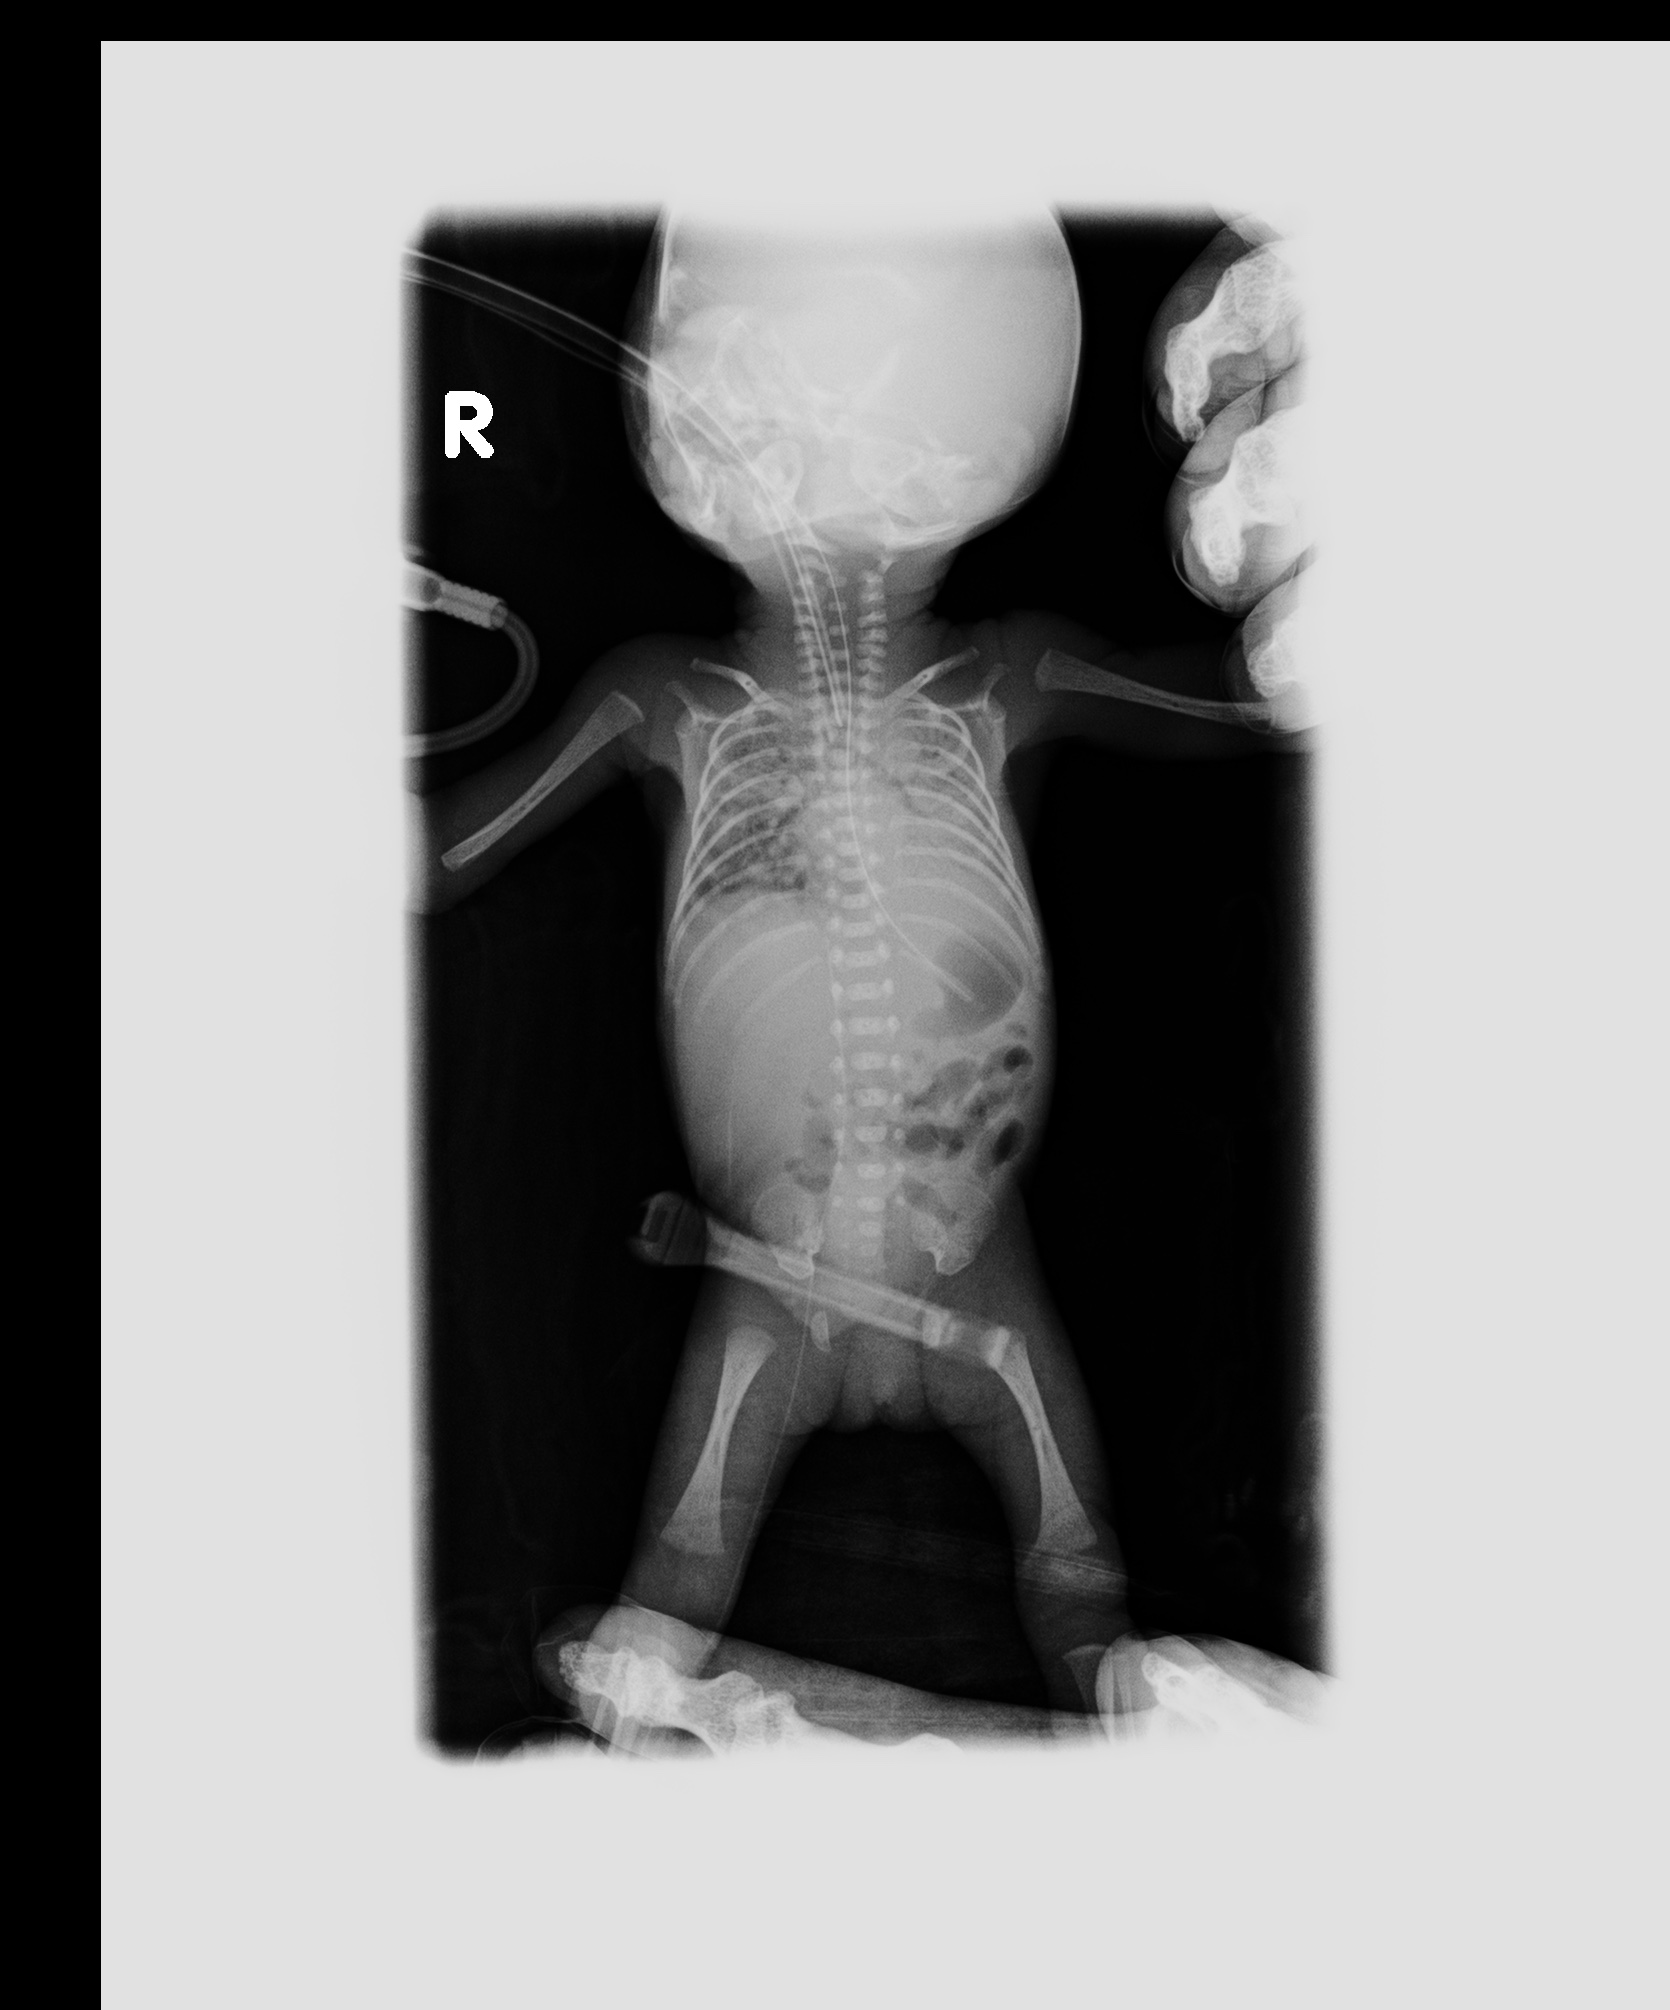

• (以下、AiCTについて)デバイス類は外されており、手を胸の前で組んでおり、エンゼルケアの後の撮影ではないかと思われる。全身皮下浮腫あり。

• 脳溝はシルビウス裂が形成されており在胎 24 週相当として平均的。両側側脳室壁には germinalmatrix が高吸収に描出されているが、これも在胎24週で出生直後として平均的。左側脳室の germinal matrix から出血しており、左側脳室内に血腫を形成し、第三脳室、 第四脳室、マジャンディ孔を介して脳槽に流出している。

• 脳実質の濃度は在胎 24 週で出生直後として平均的である。形成異常の所見、上記 IVH 以外の破壊性変化は認められない。

• IVHは存在するものの、頭蓋内には直ちに生命維持を困難とさせるような所見は認められない。

• 両側肺の含気は CT 上は全く認められない。気管・気管支を見分けることも困難。肺の CT 値は 60 程度に達している部分が広範に認められる。液面形成を示している心内腔で、血清に近い状態の腹側が CT 値 40 程度、血球成分が豊富な背側で CT 値 75 程度であることを考えると、肺出血により肺内が高吸収化しているのであろうと思われる。

• 右房内の腹側にガス粒あり(胸骨圧迫は施行されておらず、死亡確認 5 時間後 に撮影された死後 CT なので、腐敗の出現し始めかもしれない)。

• 腹部臓器は輪郭の把握も困難である。肝、両側腎が通常位置に存在している、ということが推測できるぐらい。

• 胃内にはガスと、凝血塊を思わす索状高吸収がある。積極的に腸管の虚血や壊死を疑うような腸管浮腫や壁内ガス、腹水は認めない。結腸内に相対的に高吸収の胎便が残存している。日齢 4 日目なので、消化管の動きが悪かったものと思われる。